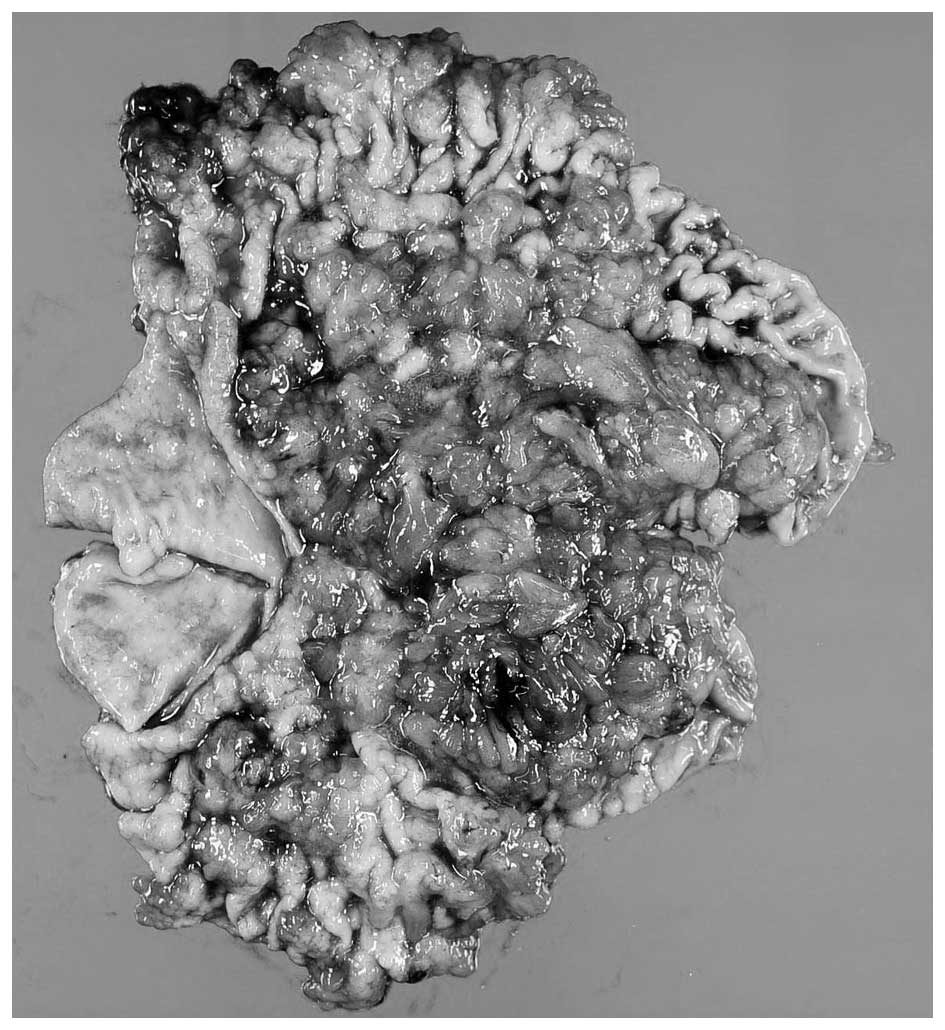

A 24-year-old man with an unremarkable medical history was referred to Onomichi General Hospital (Hiroshima, Japan) as a result of melena and anemia in 2004. An upper gastrointestinal endoscopy in 2004 revealed multiple edematous polyps around the fundus of the stomach (Fig. 1). Histological examination revealed a hyperplastic and disorganized foveolar epithelium, and an edematous lamina propria with infiltration of inflammatory cells, and the histological diagnosis was hyperplastic polyps. The patient began taking a proton-pump inhibitor and iron supplements, and he underwent an upper gastrointestinal endoscopy annually. The polyps appeared around the fundus in 2004 and had gradually progressed to the entire stomach in 2014 (Fig. 2). The number and size of the polyps had also increased. Endoscopic mucosal resection was performed frequently due to bleeding from the polyps. It was difficult to control the progressing anemia by non-surgical treatment, and, in 2014, histological examination revealed for the first time that the benign polyps were adenocarcinoma. Surgical treatment was therefore performed. At the time of surgery, the patient was 171 cm tall and weighed 62.5 kg. No skin lesions or loss of hair, which is characteristic of Cronkhite-Canada syndrome, was exhibited. Laboratory data demonstrated mild anemia (hemoglobin, 9.6 g/dl), but neither hypoproteinemia nor elevation of tumor markers, including carcinoembryonic antigen and carbohydrate antigen 19–9 was observed. With respect to the patient's family history, the patient's mother had succumbed to colon cancer in her 50s and his cousin had succumbed to an unknown primary cancer in his 30s. Colonoscopy revealed no specific findings. Enhanced computed tomography revealed that the stomach wall was edematous with enhanced thickening from multiple polyps (Fig. 3). An upper gastrointestinal series revealed that multiple polypoid lesions were limited to the entire stomach and were not present in the small intestine (Fig. 4). The patient underwent laparoscopy-assisted total gastrectomy with Roux-en-Y esophagojejunostomy. The resected specimen revealed numerous diffuse polyps throughout the entire stomach (Fig. 5). Microscopic findings revealed a hyperplastic and disorganized foveolar epithelium with an atypical nuclear shape. Enlargement of the nucleolus was also observed, and the patient was diagnosed with well-differentiated adenocarcinoma. A total of three lesions of early gastric cancer, and no lymph node metastasis were detected. Immunohistochemical staining revealed that the specimen was positive for p53 and carcinoembryonic antigen and exhibited a high index of mindbomb E3 ubiquitin protein ligase 1 (Fig. 6). The postoperative course was uneventful, hemoglobin level returned to the normal range, and the patient experienced no recurrence over a 1 year follow-up.

Figure 5.

Macroscopic findings of the resected specimen. The resected specimen exhibited numerous diffuse polyps throughout the entire stomach.